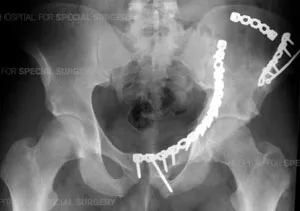

Definitive Management - Fixation Focus

Pelvic Fractures:

- Non-operative: Stable (e.g., Tile A, LC-I).

- Operative Indications: Hemodynamic instability, open Fx, symphyseal diastasis >2.5cm, vertical shear, displaced sacral Fx >1cm.

- Fixation Methods: External fixation, anterior ORIF (symphysis/rami), posterior percutaneous SI screws/ORIF.